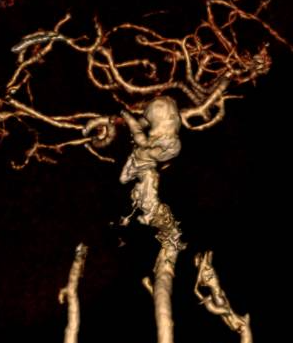

Trước tình trạng trên, các bác sĩ đã chỉ định can thiệp điều trị túi phình bằng kỹ thuật dùng stent chuyển hướng dòng chảy dưới hệ thống chụp mạch số hóa xóa nền (DSA) – một phương pháp can thiệp mạch thần kinh hiện đại, đòi hỏi trang thiết bị chuyên sâu và ê-kíp có trình độ cao.

Quá trình can thiệp được thực hiện qua động mạch đùi phải theo phương pháp Seldinger. Bệnh nhân được chụp mạch não để đánh giá chính xác túi phình. Ê-kíp đã đặt thành công stent chuyển dòng kích thước 4,25 × 20 mm qua cổ túi phình động mạch cảnh trong trái đoạn động mạch mắt. Hình ảnh sau can thiệp cho thấy stent áp sát thành mạch, che phủ hoàn toàn cổ túi phình, giảm rõ rệt dòng máu vào túi phình, đồng thời đảm bảo tưới máu não tốt, tuần hoàn não trước đạt TICI 3.

Hình ảnh thả stent chuyển dòng túi phình lớn ở động mạch cảnh trong trái dưới DSA